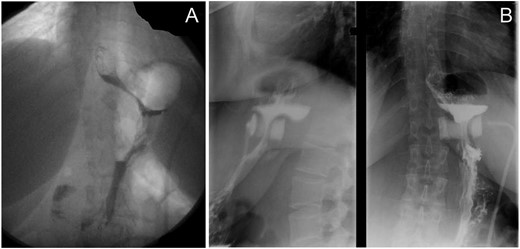

The patient became pregnant 21 months after LAGB. A monthly specialized survey was done, including systematic screening for trace metal and vitamin deficiencies. Adequate supplementation in vitamins B6, B9, B12, D, folate, magnesium and iron was provided. There was no complication of pregnancy, such as gestational diabetes mellitus, gestational hypertension nor preeclampsia, and fetal growth parameters remained within the normal range. The LAGB was kept inflated (5 ml) during the whole pregnancy, and final weight gain was 1.7 kg. Delivery of a 3,100 g male newborn occurred at 39 + 5 weeks of gestation by spontaneous vaginal delivery. Six weeks after delivery, the patient suddenly complained for total food intolerance and vomiting. Contrast meal showed an anterior band slippage, with partial stoma occlusion (Fig. 1). The LAGB could not be simply deflated and required revision, but the patient preferred to definitely remove the band, which was done under laparoscopy without surgical complication.

Contrast meal before and after pregnancy. (A) The band in good place 1 month before the beginning of pregnancy with good emptying of the gastric pouch. (B) The anterior band slippage with incomplete superior gastric pouch occlusion, 6 weeks after delivery.